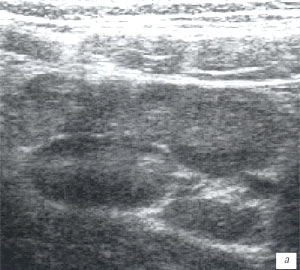

Мезентериальные лимфатические узлы: УЗИ и диагностика

Раздел: Лаборатория идей